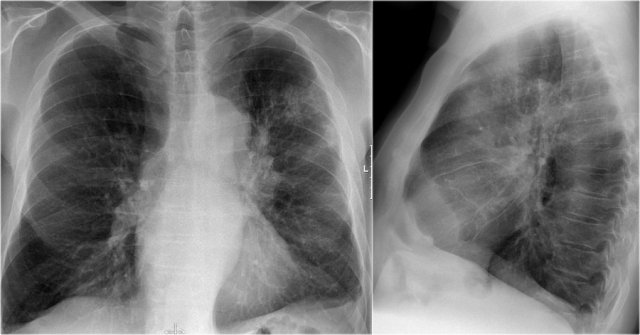

In this case there is an enlarged hilar shadow on both sides.

This could be the result of enlarged vessels or enlarged lymph nodes.

A very helpful finding in this case is the mass on the right of the trachea.

This is known as the 1-2-3 sign in sarcoidosis, i.e. enlargement of left hilum, right hilum and paratracheal.

Here some more examples of sarcoidosis.

Click to enlarge.

- Lymphadenopathy and groundglass appearance of the lungs

- Lymphadenopathy, 1-2-3 sign

- Bulky lymphadenopathy

- 1-2-3 sign

- Nodular lung pattern, no lymphadenopathy

- Hilar and paratracheal lymphadenopathy